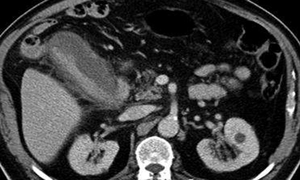

4、超声波检查

见胆囊壁增厚,胆囊缩小或变形,胆囊结石等。